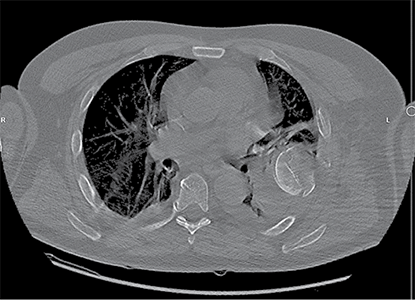

Figure 3. X-ray after shoulder arthroplasty

In a subsequent consultation, it was decided to perform shoulder arthroplasty 11 days later using reverse prosthesis (Delta Xtend, DePuy Synthes) with tuberosity fixation.

Postoperative course was uneventful in the chest or shoulder. The patient was discharged after 23 days from admition.